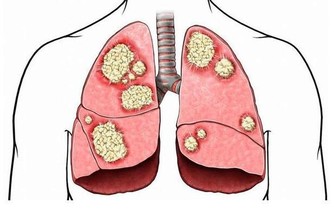

50歲的陳先生因不明原因的咳嗽去醫院就診,誰知道,做完CT檢查,竟發現是肺癌晚期。

這他難以接受甚至是惱怒,因為他每年都體檢,並且都有拍胸片,從未發現異常,為什麼現在一檢查就是肺癌晚期了?

為什麼年年體檢,卻查不出早期肺癌?

類似陳先生一樣遭遇的肺癌患者並不在少數。有人甚至將X光查肺癌稱為“最坑爹的體檢項目”,就連不少醫生也表示,用X光片篩查早期肺癌,確實不靠譜。